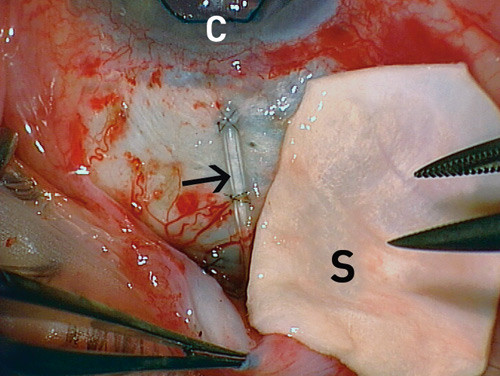

Sclera utgjør hoveddelen av øyeeplets vegg og består av kollagene og elastiske fibre. Vanninnholdet er ca. 70 %. Sclera penetreres av blodkar, men vevet er i hovedsak avaskulært. Tykkelsen er ca. 0,5 mm. Til øyekirurgi foretrekkes de tynneste delene, som befinner seg under de rette øyemusklene. Sclera kan lagres på alkohol, i glyserol eller nedfryst. Et skleralimplantat brukes ved behandling av skader i øyeveggen og ved skleral nedsmelting, som kan forekomme ved for eksempel skleromalasi ved revmatoid artritt. I tillegg kan skleralimplantat benyttes ved ventilkirurgi innen glaukombehandling. Transplantatet dekker ventilslangen (fig 3) og hindrer dermed erodering gjennom conjunctiva.